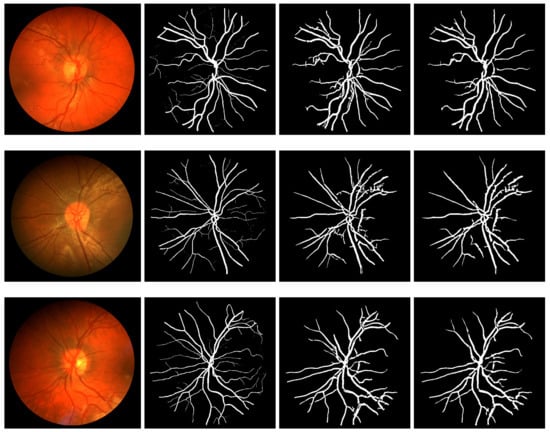

- An improved vessel segmentation framework is presented by employing the proposed ensemble S-BM3D (ES-BM3D) denoiser in the preprocessing pipeline. Specifically, we present two distinct frameworks based on each of the multiscale line detector and Frangi filter for vessel segmentation. The highlight of the proposed framework is that it is capable of segmenting vessels in presence of noise owing to the ability of the proposed denoiser to remove noise without any significant loss of vessels in the denoised fundus images. This enables the detection and segmentation of additional tiny/smaller vessels (otherwise obscured by noise) using our framework.

5.2. Retinal Vessel Segmentation Results